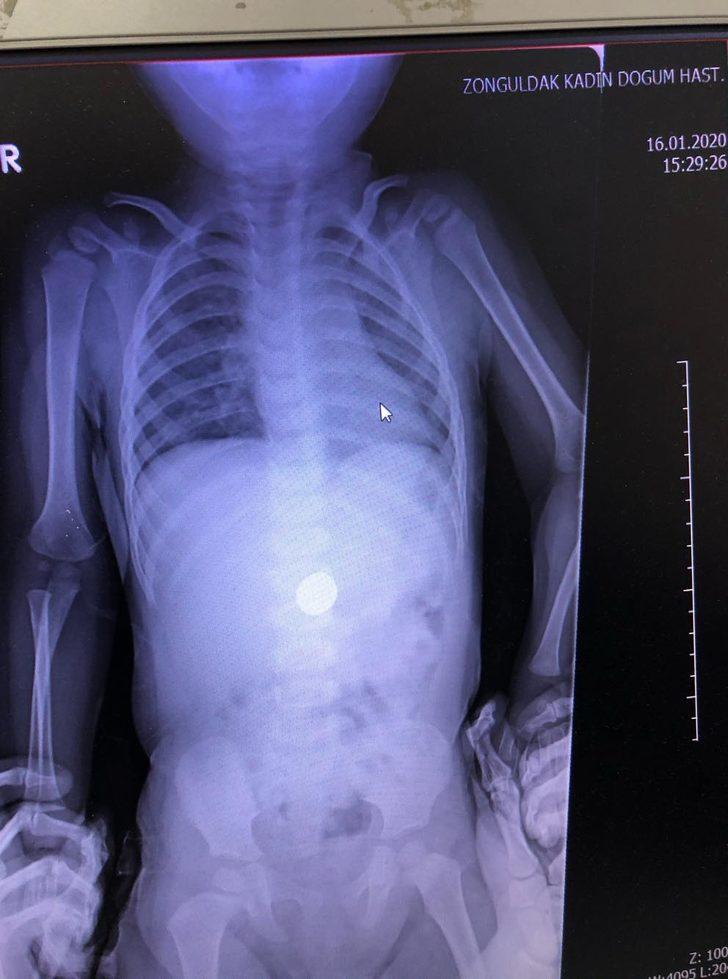

Zonguldak Kadın Doğum Çocuk Hastalıkları Hastanesi'ne 16 Ocak'ta başvuran aile, doktorlara çocuklarının madeni para yuttuğunu söyledi. Dr. Sertaç Akman, çekilen röntgende E.İ. isimli erkek çocuğun midesindeki 25 kuruşluk madeni parayı tespit etti. E.İ.'nin yapılan muayenesinde madeni paranın yemek borusuna zarar vermediği anlaşıldı. Doktorlar, gerekli tetkikleri yaptıktan sonra E.İ.'nin parayı doğal yollarla çıkarması için taburcu edip evine gönderdi. Takibe alınan E.İ.'nin normal yolla parayı çıkaramaması halinde endoskopi veya ameliyat gibi farklı yöntemlerle paranın çıkarılabileceği öğrenildi.